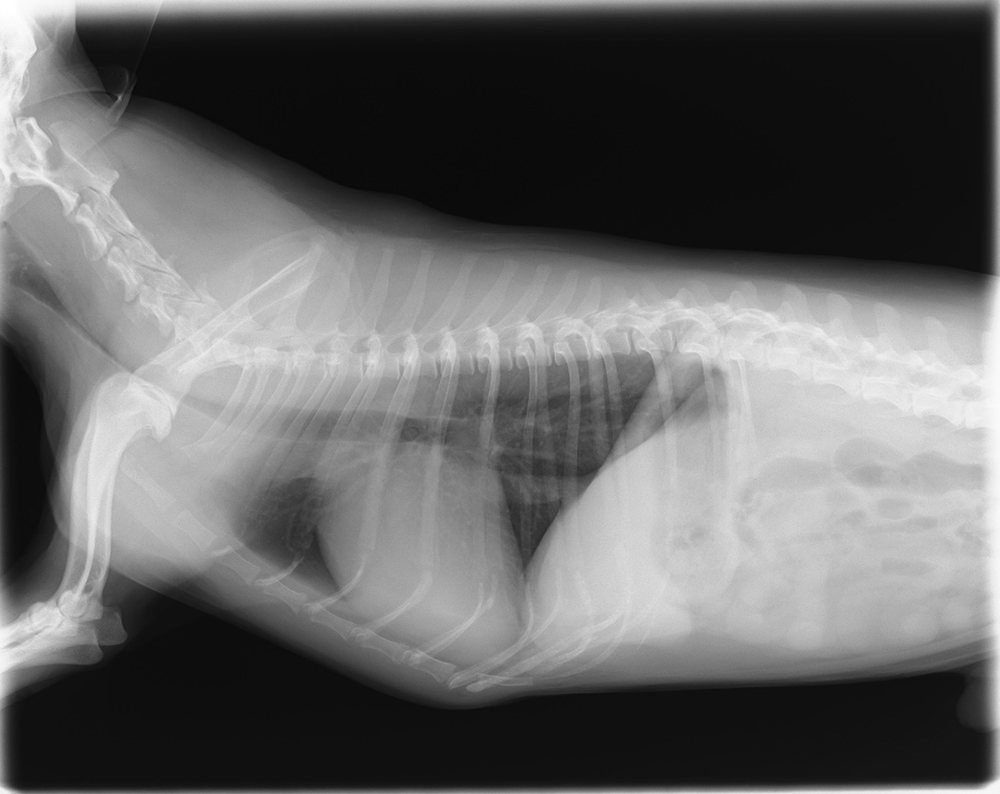

胸部レントゲン検査

胸部レントゲン検査は、呼吸器の病気について最も短時間で行うことができ、得られる情報量の多い検査です。

健康診断でご自身のレントゲン画像を見たことのある方も多いのではないでしょうか。人間のレントゲン検査と同じように、動物の体を透視したような画像を写すことができます。

レントゲンが呼吸器疾患の診断に適しているのは、レントゲンの画像が白黒の濃淡を、空気と臓器でそれぞれ異なって写すことができるためです。体の中で唯一空気を含んでいる呼吸器では、色のコントラストにより異常を判断することができます。レントゲン検査は、呼吸器のある胸の構造を観察するのに非常に有効です。

検査自体は短時間で行うことができますが、画像を撮影するのに体を抑える必要があります。犬や猫が体を抑えられることで興奮してしまうと、呼吸状態が悪い場合は命に関わることがあるため、当院では慎重に検査を行っています。